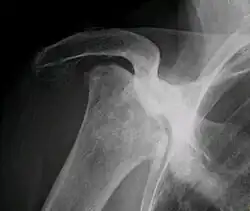

Necrose avascular

Necrose avascular, também é conhecida como osteonecrose, necrose asséptica ou necrose isquêmica do osso, é uma doença causada pela perda temporária ou permanente da irrigação de sangue aos ossos. A morte do tecido ósseo causa seu colapso resultando em dor e deficiência.